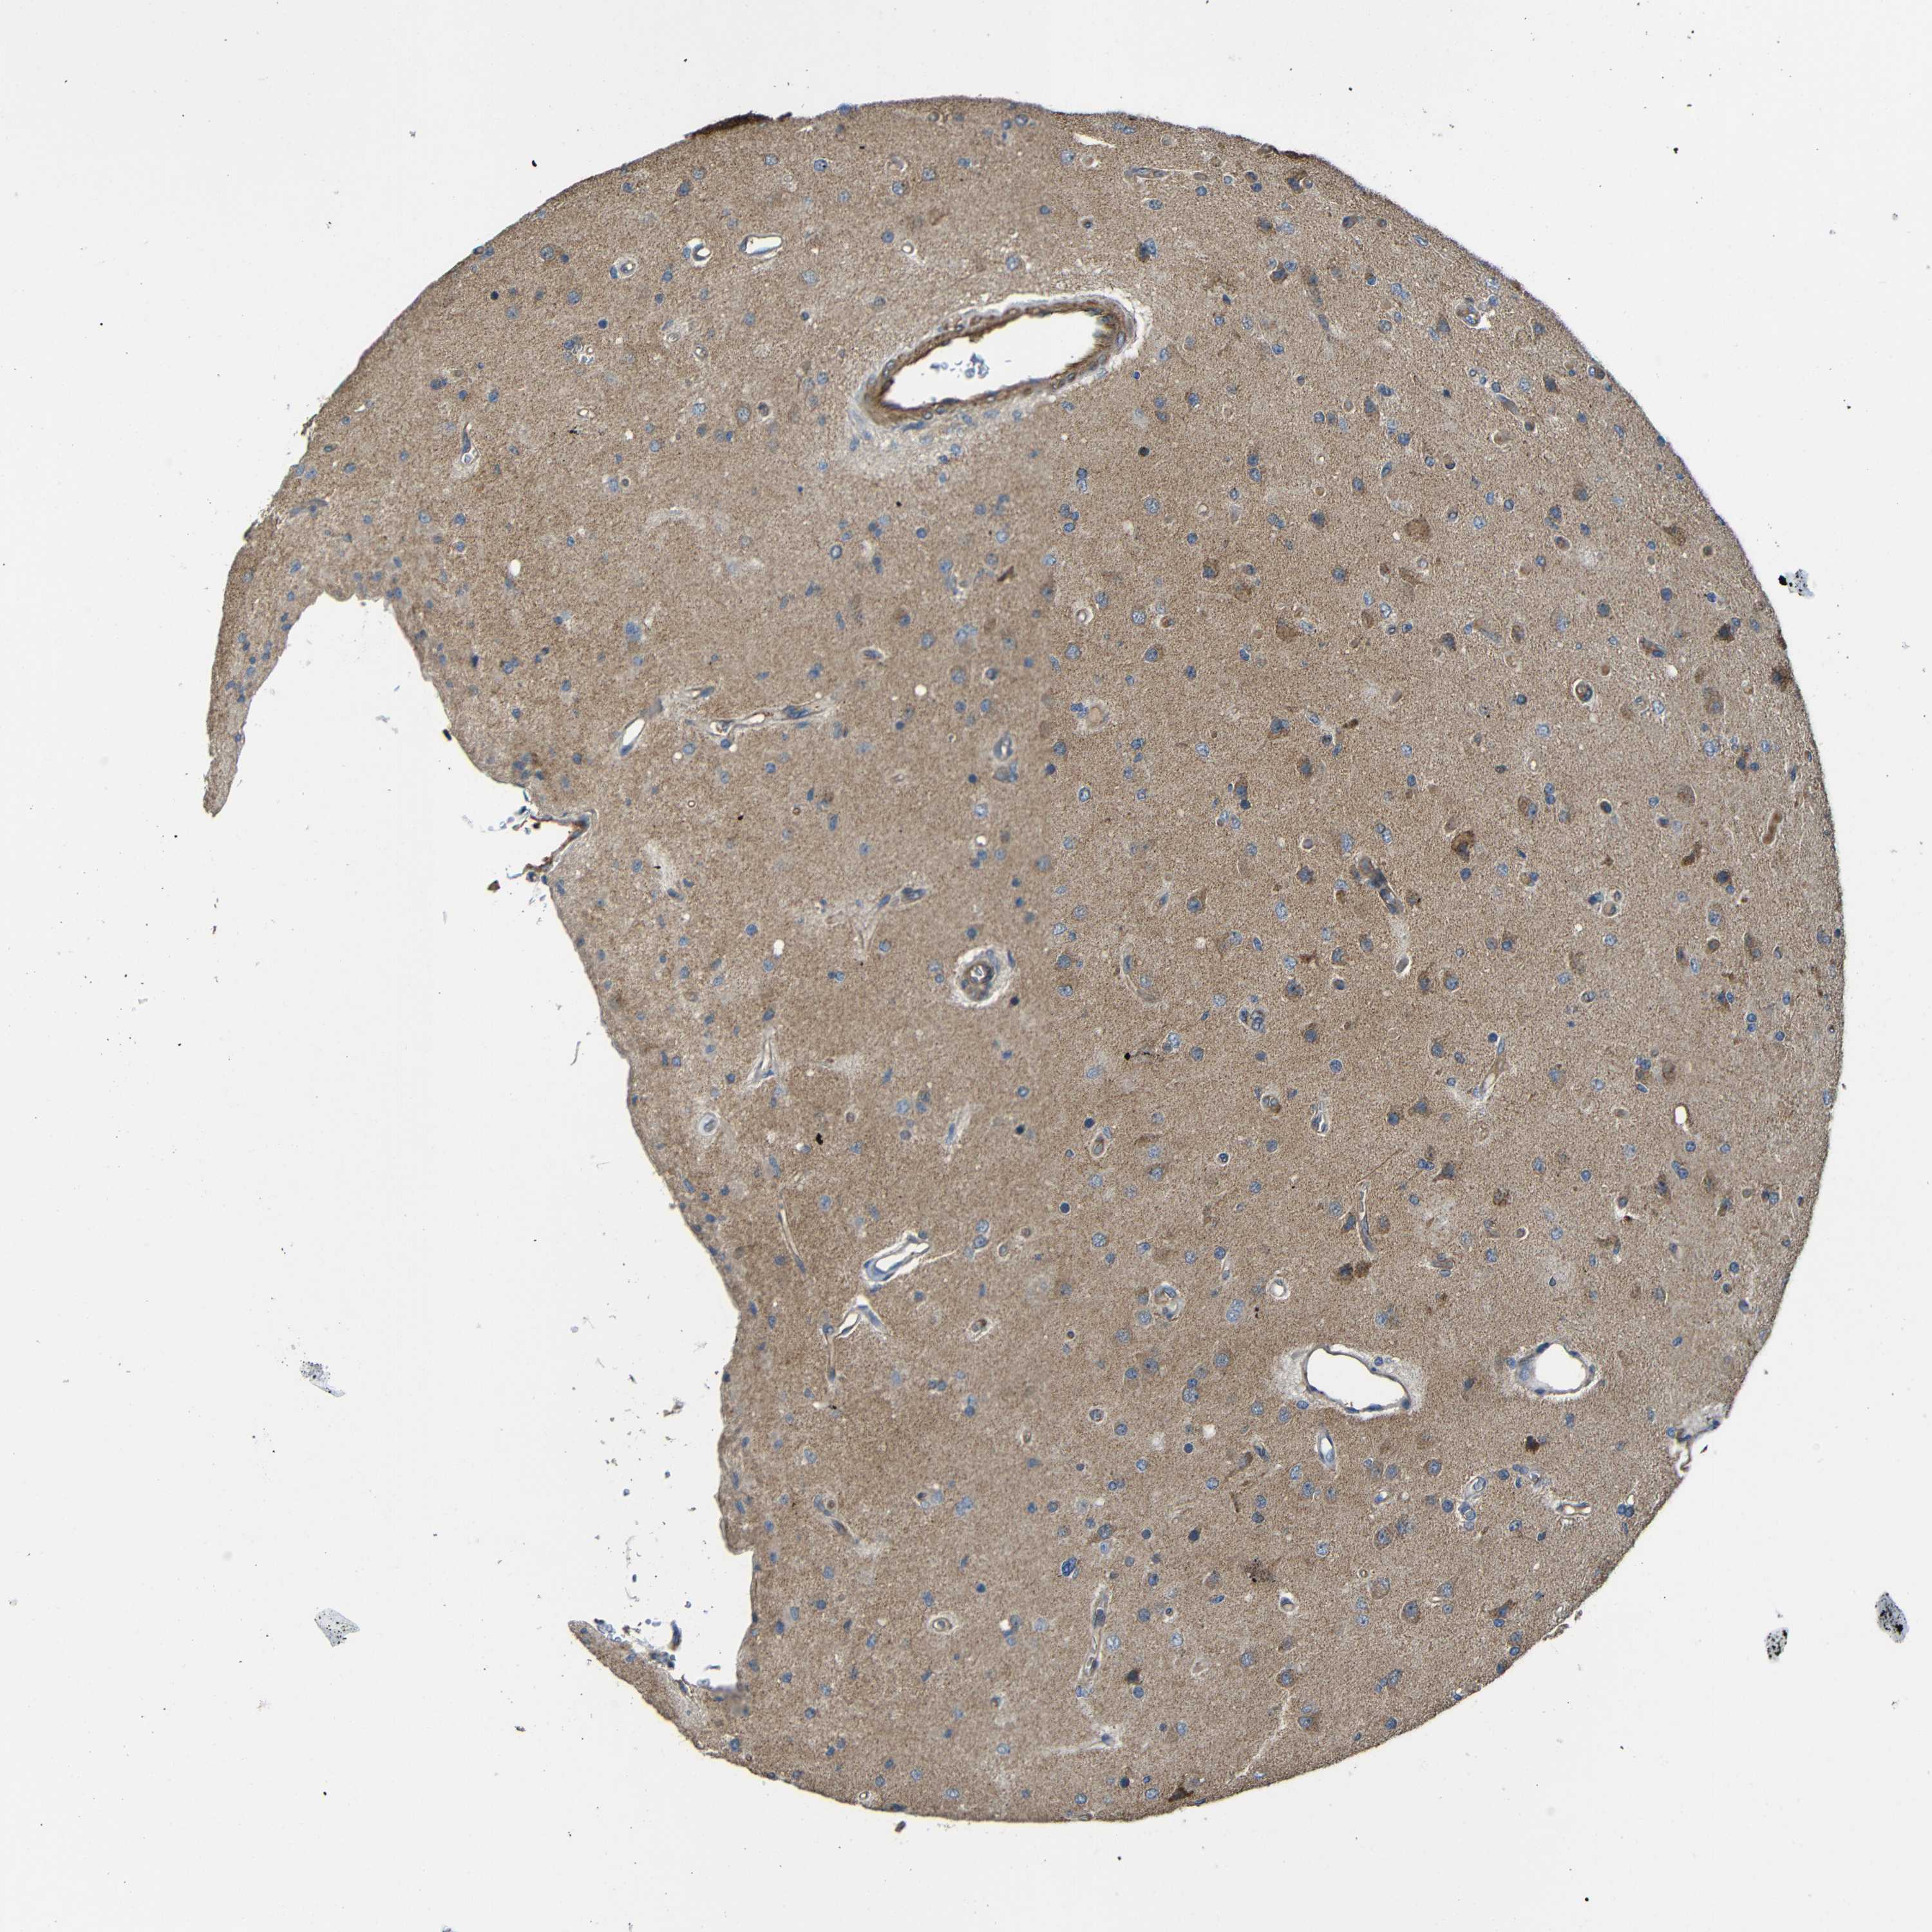

GLIOMA - Protein expressioni

A mouse-over function shows sample information and annotation data. Click on an image to view it in a full screen mode. Samples can be filtered based on level of antibody staining by selecting one or several of the following categories: high, medium, low and not detected. The assay and annotation is described here.

Note that samples used for immunohistochemistry by the Human Protein Atlas do not correspond to samples in the TCGA dataset.

Antibody stainingi

Antibody staining in the annotated cell types in the current human tissue is reported as not detected, low, medium, or high, based on conventional immunohistochemistry profiling in selected tissues. This score is based on the combination of the staining intensity and fraction of stained cells.

Each image is clickable and will lead to virtual microscopy that enables deeper exploration of all samples and also displays staining intensity scores, fraction scores and subcellular localization as well as patient and tissue information for each sample.

Antibody CAB013717

Staining

High

Medium

Low

Not detected

Intensity

Strong

Moderate

Weak

Negative

Quantity

>75%

75%-25%

<25%

None

Location

Nuclear

Cytoplasmic/membranous

Cytoplasmic/membranous,nuclear

Glioma, malignant, High grade

Glioma, malignant, Low grade